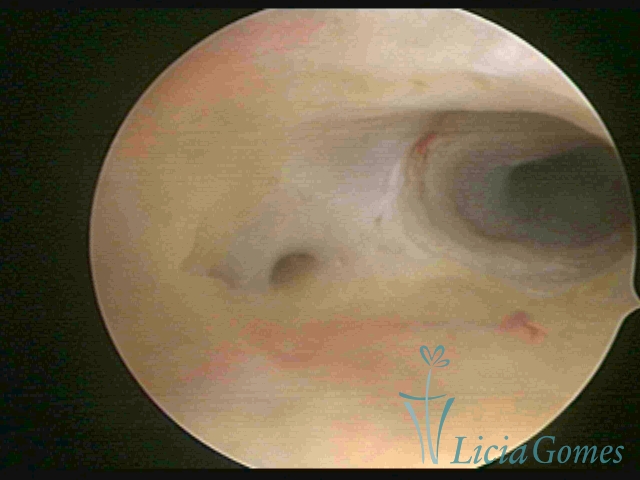

Second part or middle section

In the middle section of the cervical canal, the details of the buds are lost. It is possible to view creases and crypts. Longitudinal grooves are frequently observed. They are the most compact tissues presenting the most vascularized surface, whose vessels follow its passageway.